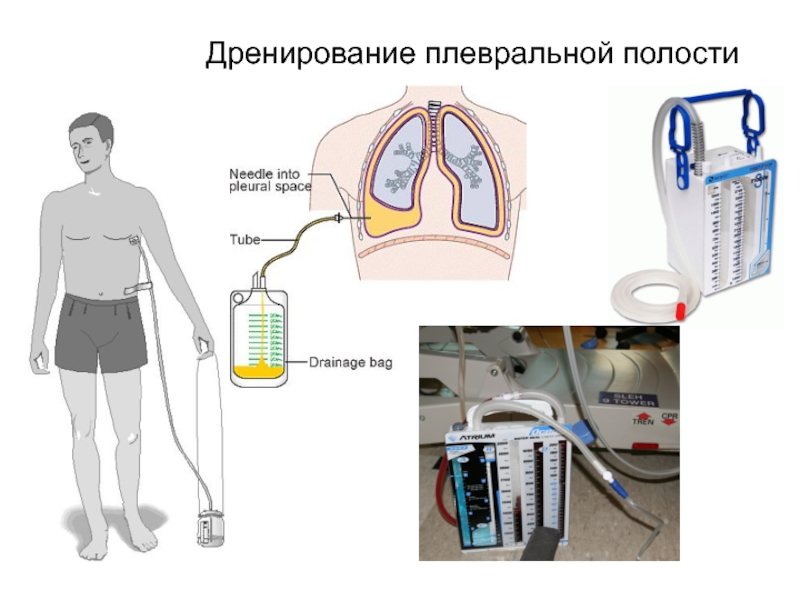

Схемы дыхания: Пневмоторакс на изображениях